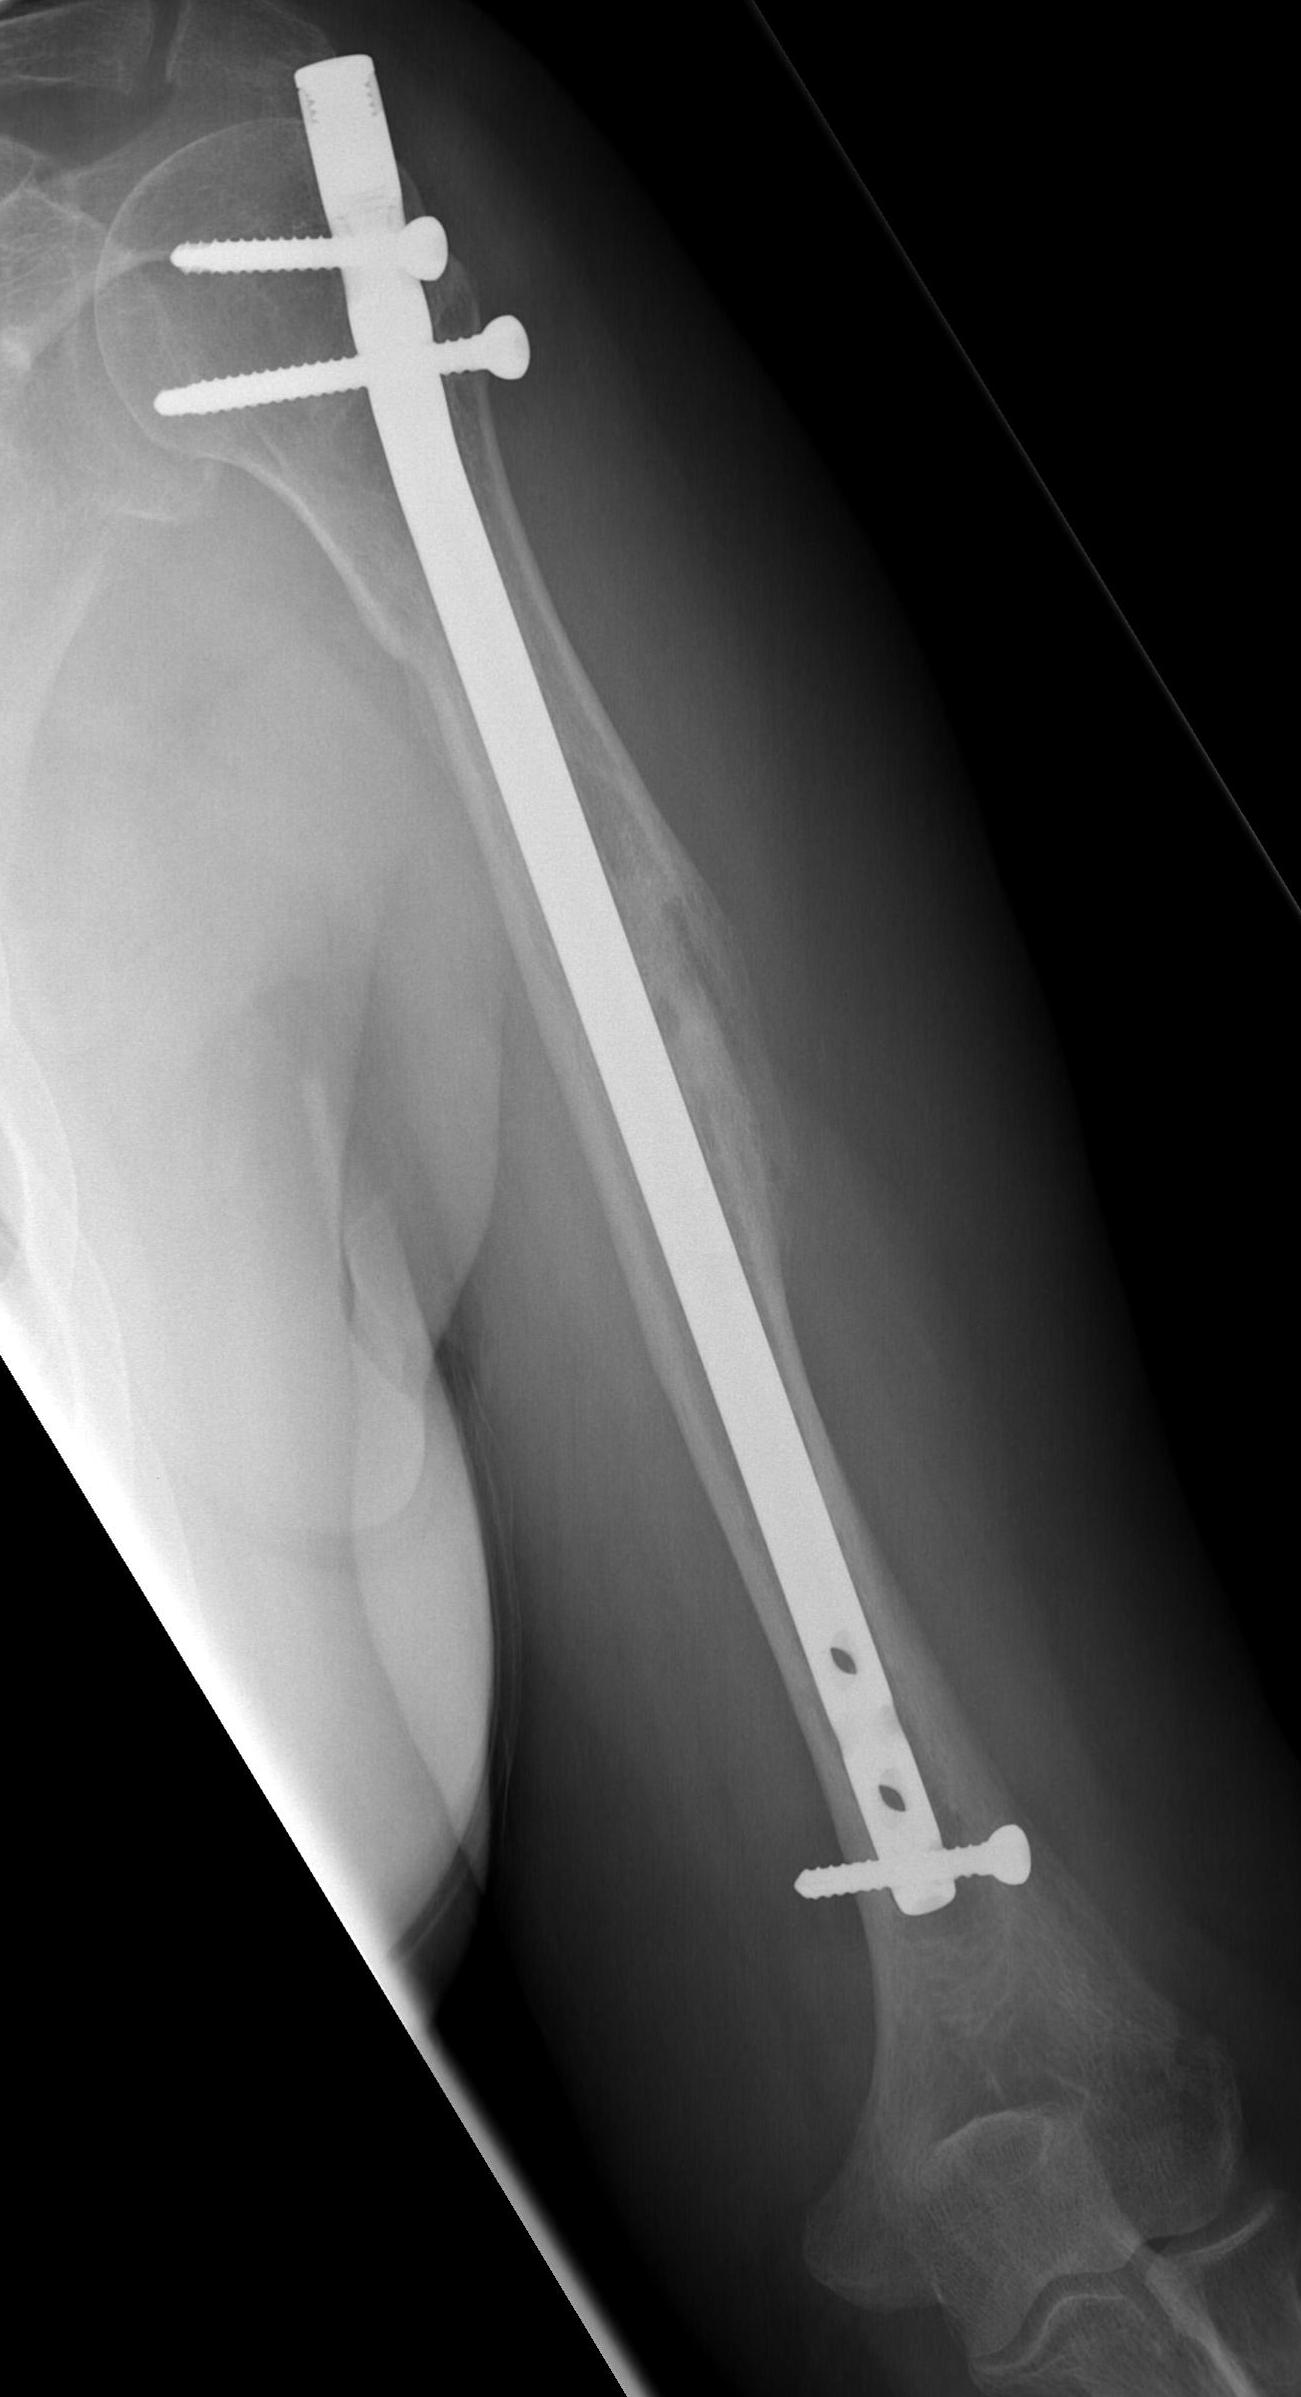

What humeral IM nail is this?

Does anyone know what humeral IM nail this is?

This patient presented to my office the other day after having her humeral shaft fracture treated with this IM nail in the Ukraine.

Limited ROM and shoulder pain.

Not hard to figure out why.

It's like a Medgal humeral nail.

I think You will have no problems to remove screws ( standard cortical 6-border unscrew). To remowe the nail You have about 2 cm over capitus humeri. If it Medgal - the proximal carving is M10 x 1.

I agree with Dr.Zubach, it's like a Medgal humeral nail. However it's seems to me the diameter of removal screw is not 10 mm. I would refer you to Medgal's site http://www.medgal.com.pl/